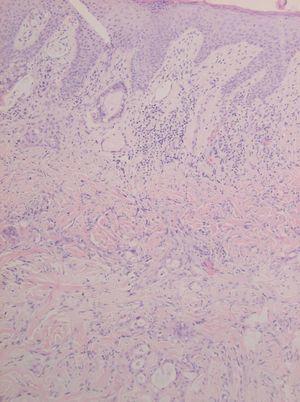

El estudio histológico de una biopsia de la lesión se muestra en las figuras 2 y 3.

Fig. 2.--Detalle histológico. (Hematoxilina-eosina, x 20.)

El examen histopatológico muestra una dermis con numerosas formaciones glandulares (fig. 2). A mayor aumento se aprecia que las formaciones glandulares están constituidas por células poligonales y cilíndricas con presencia de moco en su interior, con núcleos pleomórficos e hipercromáticos, y con presencia de nucleolos. El estudio inmunohistoquímico demuestra una positividad para el antígeno carcinoembrionario (CEA) (fig. 3) y la citoqueratina (CK) 20, siendo negativa la CK7. El resultado de la biopsia de la neoformación colónica revela la presencia de un adenocarcinoma bien diferenciado, con áreas coloides, infiltrante, sobre adenoma velloso.